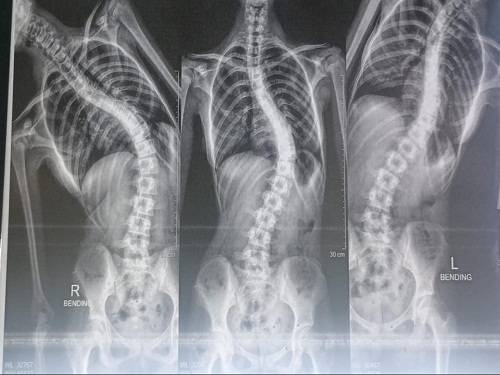

قام فريق جراحة العمود الفقري بمستشفى جامعة الفيوم بقيادة الدكتور/ محمود بهلول (استشاري جراحة العظام والعمود الفقري) بإجراء جراحة استعدال تشوه شديد في العمود الفقري (تحدب وجنف جانبي) باستخدام تقنية التثبيت الداخلي للفقرات بواسطة مسامير وأعمدة وتم إجراء الجراحة تحت متابعة جهاز وظائف الأعصاب الطرفية وهو تقنية حديثة جداً لاستنباط أي تأثر للأعصاب الطرفية أثناء إجراء الجراحة وقد أفاد الدكتور/ محمود بهلول بأن الجراحة تمت بنجاح والمريضة خرجت سليمة معافاة وتكون الفريق الطبي من الدكتور/ محمود بهلول، والدكتور/ محمود حسين مدرس جراحة العظام، والدكتور/ محمد جمال الزيات مدرس مساعد جراحة العظام، والدكتور/ حمدي عادل مدرس مساعد جراحة العظام، وطبيب التخدير الدكتورة/ عبير شعبان مدرس التخدير، والدكتور/ محمد العشيري مدرس مساعد التخدير، والأستاذ/ محمود سيد شعبان من قسم التمريض وتعد هذه الجراحات النادرة من الحالات المهارية التي تحتاج إلى مراكز جراحية من الدرجة الثالثة وهو الدور الذي تقوم به المستشفيات الجامعية وقد صرح الدكتور/ محمد ياسين مدير مستشفى الجراحة بأن المستشفى الجامعي تهتم اهتمامًا شديداً بالجراحات النادرة التي كانت تستدعي سفر المرضى إلى محافظة أخرى خارج الفيوم لإتمامها.